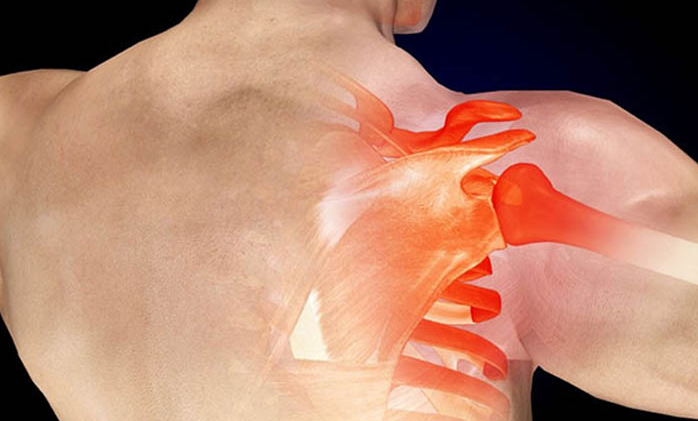

견갑골은 등 상부에 위치한 삼각형 모양으로 상완골을 쇄골과 흉벽에 연결하는 역할을 합니다. 어깨의 움직임에서 가장 중요한 역할을 하는 부분이기도 합니다.

어깨는 비교적 활동범위가 넓어 다치기 쉽습니다. 이때 견갑골은 필연적으로 영향을 받아 통증과 불편함을 유발합니다. 그러나 어떤 경우에는 견갑골 통증이 단순한 신체적 부상 이상입니다.

견갑골 통증은 다양한 요인에 의해 경추 척수의 감각 신경계 장애로 인한 것으로 생각됩니다. 이 상태는 누구에게나 발생할 수 있으며 특히 어깨 힘을 자주 사용하는 사람들에게 발생할 수 있습니다. 적절한 치료와 재발 방지를 위해 올바른 원인을 파악하는 것이 필요합니다.

1.3. 견갑골 부상

견갑골 통증 원인 - 충돌, 낙상, 작업 중 골절, 스포츠 및 일상 활동으로 인한 어깨 부상을 입은 사람들도 치유 후 통증이 재발할 수 있습니다. 그 이유는 환자가 몸을 관리하고 돌보는 데 신경을 쓰지 않고, 너무 힘들게 일하고, 무거운 물건을 들거나, 과식을 하고, 초기에 견갑골의 쇠약과 통증을 유발하기 때문입니다.

견갑골 통증 원인 - 견갑골 통증은 경추 손상과 관련이 있을 수 있습니다. 일반적으로 추간판 탈출증, 경추증, 선천적 추간판 붕괴등 접합부에서 경추 손상은 척수 신경을 압박하고 이 신경의 신경 분포에 따라 통증을 자극합니다.